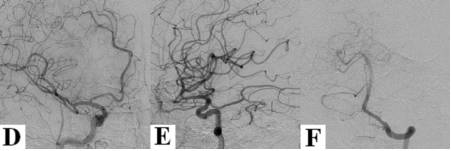

病例1:64岁女性患者,抽烟,既往高血压病史。因突发剧烈头痛入院,神经系统查体阴性。头颅CT提示颅底脑池内对称性、弥漫性SAH(图1A)。颈部CTA提示右侧锁骨下动脉近端重度狭窄,可见一钙化斑块起源于头臂干;此外,于右侧颈内动脉发现一钙化溃疡斑块(图1B和1C)。次日及1周后的DSA检查均未见颅内血管性病灶(图1D-F);右侧锁骨下动脉盗血明显,致使血流完全经右侧椎动脉逆转(图1G和1H)。第10天查MRI-DWI相上发现多发小梗死灶,分布于右侧大脑中动脉供血区和双侧扣带回(图1I-P)。患者诊断为右侧颈内动脉起源的颅内动脉血栓栓塞。给予阿司匹林口服后好转出院。

图1. A. 头颅CT显示弥漫对称的脑池SAH;B、C. 颈部血管CTA显示钙化的动脉粥样硬化斑块,导致右侧锁骨下动脉近端严重狭窄(B图箭头)和右侧颈内动脉起源处钙化溃疡斑块(C);D-H. DSA排除动脉瘤或血管畸形(D-F),DSA见右侧锁骨下动脉盗血现象,血流在右侧椎动脉逆流(G和H);最后2排MRI- DWI成像,显示右侧大脑中动脉供血区和双侧扣带回多发小弥散受限病灶。